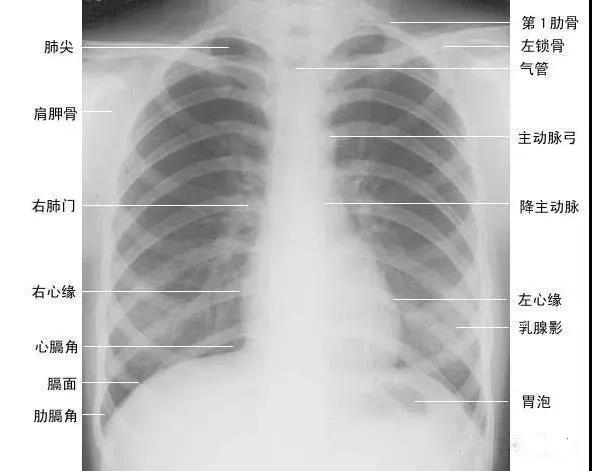

正常胸廓由软组织与骨骼组成,两侧对称(如下图)。

(一)软组织 1、胸锁乳突肌及锁骨上皮肤皱褶 胸锁乳突肌起自胸骨柄及锁骨内端,向后上方斜行,止于乳突,在两肺尖内侧形成外缘锐利且较均匀的致密阴影。在胸骨头和锁骨头及锁骨之间形成一个小三角间隙,叫锁骨上窝或胸锁乳突肌间隙。当颈部偏斜时,两侧胸锁乳乳突肌阴影可不对称,勿误为肺尖部病变。锁骨上皮肤皱褶为与锁骨上缘平行的薄层软组织影,其厚度为3~5mm,内侧与胸锁乳突肌阴影相连,略成直角,系锁骨上皮肤及皮下组织的投影。

2、胸大肌起于锁骨的外侧分,胸骨和第1~6肋软骨,肌束行向外上方,至于肱骨大结节嵴。在肌肉发达的男性,于两肺中部的外侧形成扇形均匀致密影,下缘锐利呈斜行曲线,自肺野伸向腋部,与腋前皮肤皱褶相延续。

3、乳房及乳头 女性乳房于两下肺野形成半圆形的密度增高影,其下缘清楚,并向外与腋部皮肤连续,上缘不清,且密度自下而上逐渐变淡以至消失,其位置随年龄的增长而下垂,一般两侧对称。乳头在两下肺野相当于第5前肋间处形成边缘清楚的小圆形致密阴影,乳房越薄,乳头影境界越清晰,其特点亦为左右对称。青春期乳头呈半球状,约在第2~6肋之间。妊娠期乳腺可明显增大,至哺乳期结束后,乳房逐渐缩小,失去弹性而下垂,到老年期,乳房逐渐萎缩。

(二)骨骼 胸廓前有胸骨、锁骨,后有胸椎、肩胛骨,肋骨则围绕其间。

1、肋骨共12对,每根肋骨分为前肋、腋段和后肋三段:同一肋骨前后段的位置不同,一般第6前肋与第10后肋等高。前段扁薄,密度略低,自外上向内下倾斜走行并形成肋弓;后段圆厚,密度略高。呈水平状向外下走行;在无变异的情况下,两侧肋骨的位置及肋间隙的宽度基本对称,故肋骨及肋间隙常被用作胸部病变的定位标志。第1~10肋骨前端有肋软骨与胸骨连接,因肋软骨未钙化时不显影,故肋骨前端多呈游离状。25岁以后第1对肋软骨首先钙化,其他肋软骨随年龄增长,自下而上逐条钙化。第一肋骨常常显示不规则钙化区,尤其是中年以后。下部诸类也显示局限性的钙化,即使在成年人也是这样。在女性的软骨钙化常常示不规则的,造成斑点状形态。而在男性钙化可以局限于软骨之上下缘,造成线样阴影。有时下肋部肋软骨的钙化极为广泛,造成下肺野内带不规则的斑点状致密影。肋骨有很多种先天变异(下图),常见的有以下几种:

在常规前位x胸片上,肋骨特别是其后部非常分明,第一肋骨的前端宽大恰好位于锁骨水平之下,由此可以识别,也可以借助和他构成关节的第一胸椎至关系来识别。第一胸椎和第七颈椎的鉴别可由他们的横突方向来判断,前者横突下上,向外倾斜,而后者横突指向下外方。这种鉴别对于有颈肋者颇有价值,因为有时颈肋很长与第一肋骨极为相似。

2、肩胛骨在标准后前位胸片上,应投影于肺野之外,如两肩向前旋转不够或于前后位,尤其是卧位投照时,胛骨影可呈带状重叠于中上肺野的外侧部。

3、锁骨 在标准后前位胸片上,两侧锁骨内端亏蝇骨柄形成胸锁关节,该关节到中线的距离应相等:两侧锁骨外端与肩峰形成肩锁关节。

4、胸骨 在标准后前位胸片上,大部分胸骨与纵隔阴影重叠,仅胸骨柄两侧外上缘可突出于纵隔影之外,投照位置略有偏斜时尤为常见,其在侧位和斜位片上可全貌显示。

5、胸椎在标准后前位胸片上,胸椎位于纵隔阴影内,透过气管影可清晰显示第1~4胸椎,而心脏后方的胸椎仅隐约可见。

1、正位肺门影后前位胸片上,肺门位于两肺中野内带第2~4前肋间处,通常左侧肺门比右侧高1~2cm,两肺门的大小和密度大致相等。